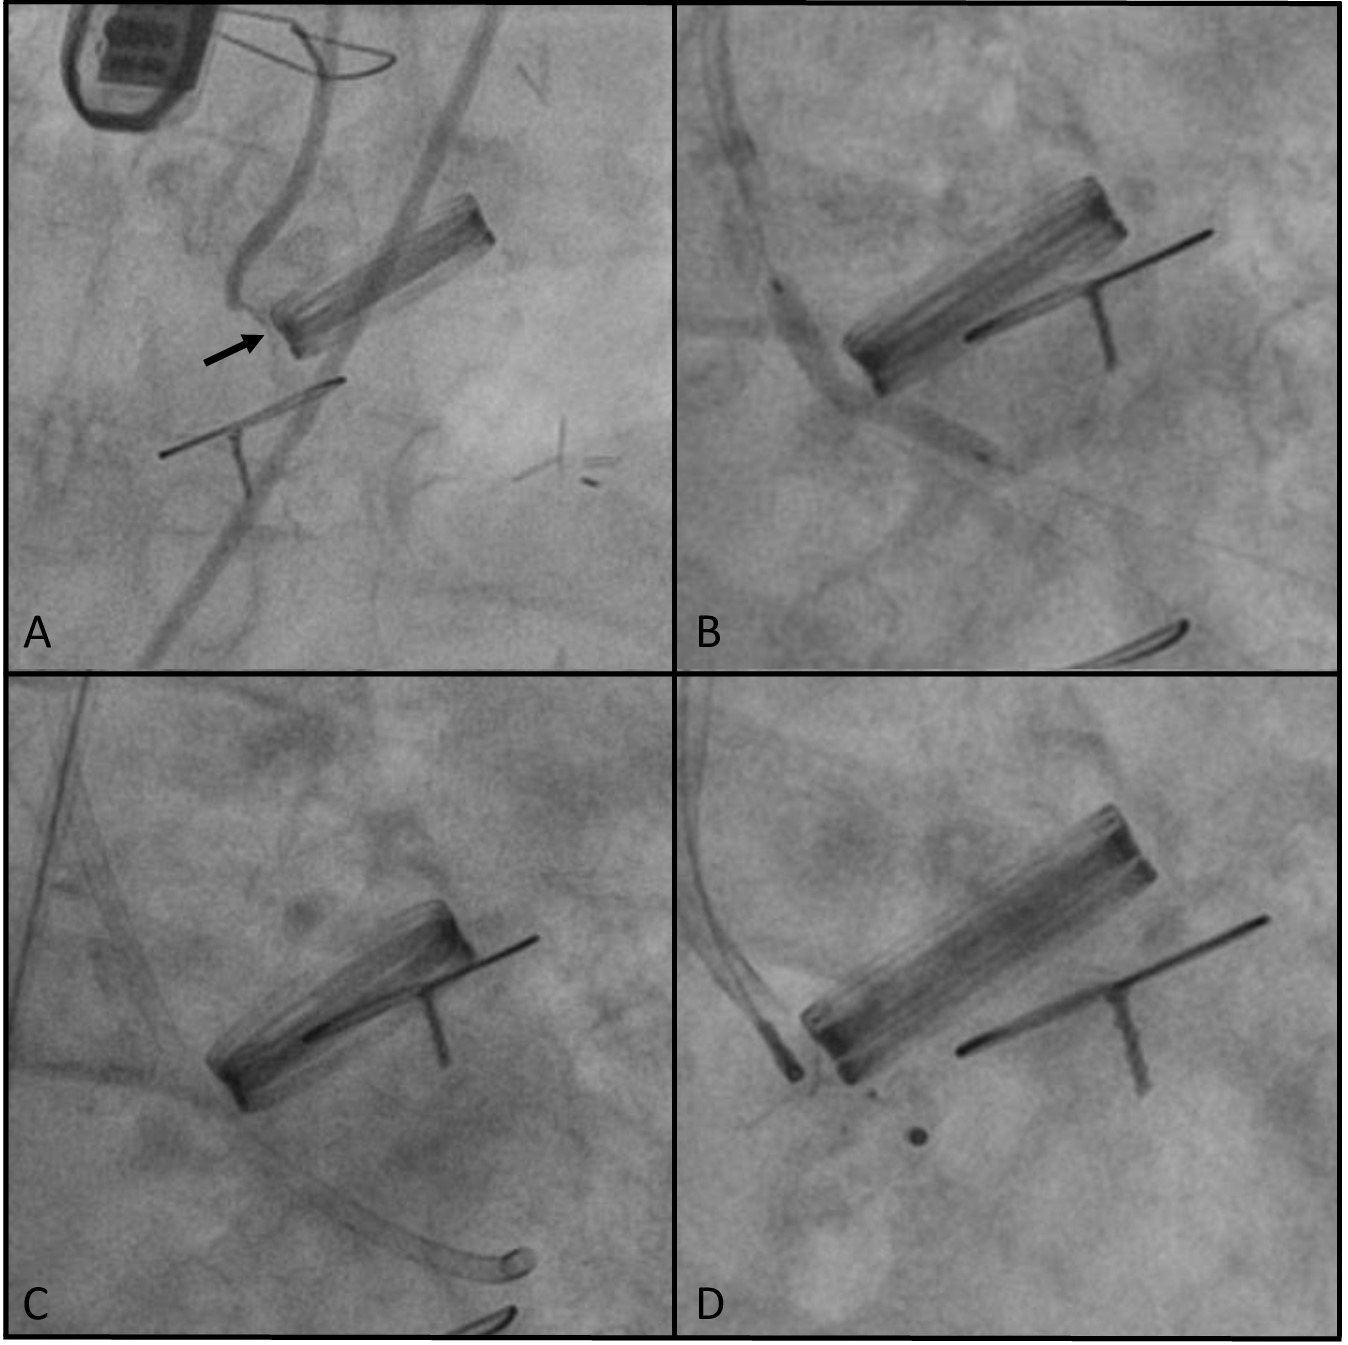

The study is a registry of all transcatheter PVL closure procedures performed in 3 high-volume centers in which predilation of the channel lumen was performed using a noncompliant coronary angioplasty balloon after a failed attempt to navigate the delivery sheath through the PVL channel. The size of the balloon was estimated to correspond to the outer diameter of the intended delivery sheath, which was the sheath with the smallest diameter allowing for the planned occluder implantation. The technique for using the angioplasty balloon involved positioning it within the PVL channel such that the distal part of the balloon remained within the delivery sheath, while the remainder of the balloon was used to dilate (smoothen) the lumen of the PVL channel. After achieving balloon expansion, the sheath was advanced over the deflating balloon through the PVL channel (Figure). All subjects gave their informed consent for the interventions described in the manuscript, and the study was conducted in accordance with institutional guidelines.

In most cases, the occluders were implanted using a 6F coronary guiding catheter for delivery, and a 2.0-mm balloon was utilized to facilitate passage through the PVL channel. The difficulties encountered with the delivery catheter were due to the small size and unfavorable shape of the PVL channel (slit-like), which often also had a tortuous course along its long axis. The balloon catheters were inflated under fluoroscopic guidance until full expansion with no waist was achieved. This did not require the application of pressures exceeding those that are standard for regular angioplasty balloons, nor were high-pressure balloons used. In 1 instance, the operator opted to use a balloon with a diameter that exceeded that of the delivery sheath, specifically a 3.0-mm balloon for a 6F sheath. The use of this balloon was preceded by an attempt to navigate through the PVL channel with a 2.0-mm balloon, which proved to be ineffective. In each case, the occluder was implanted in the size that was originally planned. There was no need to increase the size of the occluder after balloon predilatation. No periprocedural complications or clinical signs of central/peripheral embolism were observed during the procedure. During the post-procedural hospitalization, 2 patients experienced complications unrelated to the assessed technique.